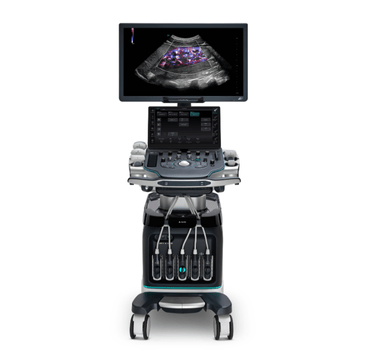

Mindray Ultrasound Machines

Ultrasound is a game-changing solution as the healthcare industry faces pressure to improve patient outcomes and reduce costs. MindrayŌĆÖs cutting-edge ultrasound machines offer a more cost-effective, real-time, and patient-friendly imaging alternative, with innovative technologies that can help improve patient outcomes and reduce costs. Explore our range of ultrasound machines, tailored to meet the needs of various medical departments.

Our Cutting-Edge Technology Evolves to Meet Healthcare Needs

MindrayŌĆÖs exclusive Living Technology? guarantee will secure your product investment by ensuring that your system remains at the cutting-edge of imaging performance excellence. Living Technology is a constantly evolving, software-based approach to providing our partners with easily upgradable enhancements made possible with our core imaging technologies: ZST+, X-Insight, and mQuadro.